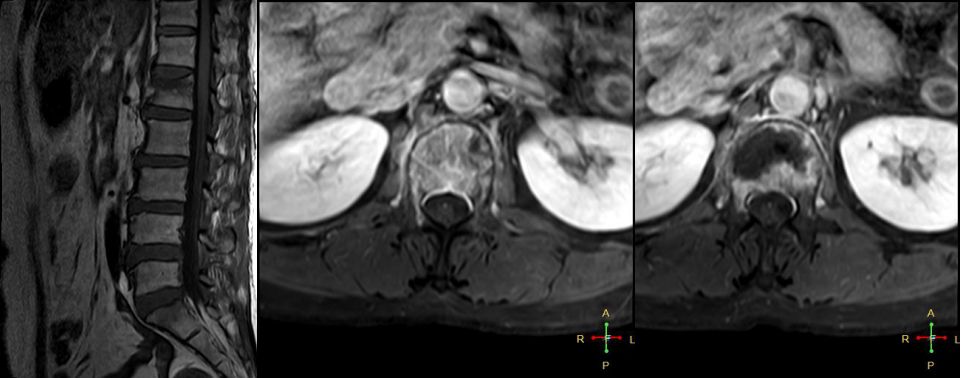

3 恶性压缩性骨折 椎体上下径变窄而前后径增大,椎体后部皮质后突,后角一般表现圆钝,无上翘,常呈球形突出,致椎管狭窄,即膨胀性盘状破坏,硬膜囊和脊髓受压。

——恶性压缩性骨折MR信号特点—— 由于肿瘤组织的侵犯,T1WI上椎体呈弥漫性低信号,T2WI呈高信号,增强扫描呈明显不均匀强化。

转移瘤 椎弓根改变:椎弓根膨大仅见于恶性压缩性骨折,故为其特异性,可作为鉴别诊断的依据。

椎旁软组织肿块:在转移瘤中,受累椎体周围多出现分叶状或肿瘤样软组织肿块,此征象仅见于恶性压缩性骨折。故,椎旁薄环状软组织与瘤样软组织肿块是鉴别骨折性质较有特征性的征象。

——恶性压缩性骨折—— 扁平形或倒楔形 跳跃性分布(转移瘤) 椎间盘不受累 T1WI均匀低信号 后角圆钝,膨胀性盘状破坏 椎弓根受累、膨大 椎旁分叶状及肿瘤样软组织肿块